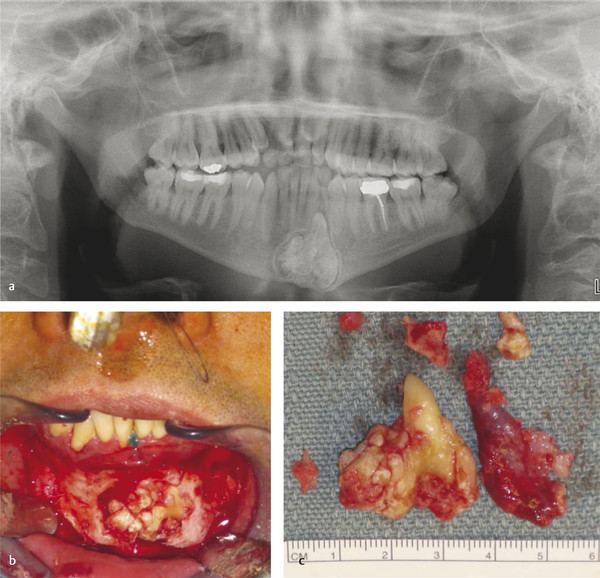

9.4.6 Ameloblastic Fibro-odontoma

Ameloblastic fibro-odontoma (AFO) is usually seen in teenagers as an asymptomatic jaw expansion that may resorb adjacent teeth. It has a mixed radiolucent–radiopaque presentation and is radiographically similar to a developing odontoma (Fig. 9‑9a). Majority of these tumors are found in the posterior mandible and are often associated with an unerupted tooth. Treatment includes simple enucleation and curettage (Fig. 9‑9b, c). Prognosis is excellent, and recurrence is rare.